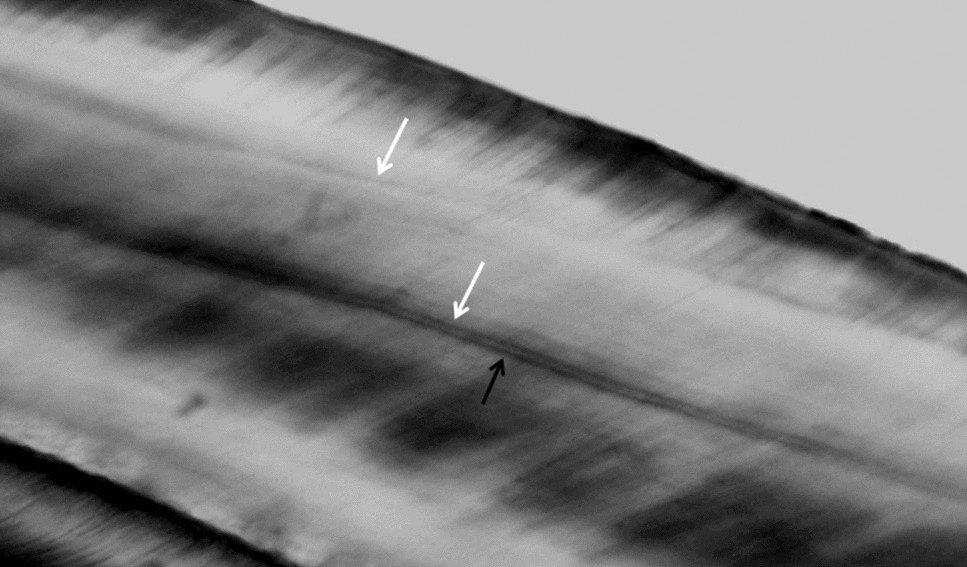

Figure 5

Accentuated lines (white arrows) in enamel of incisor. Note the neonatal line nearby (black arrow) (magnification 40x).